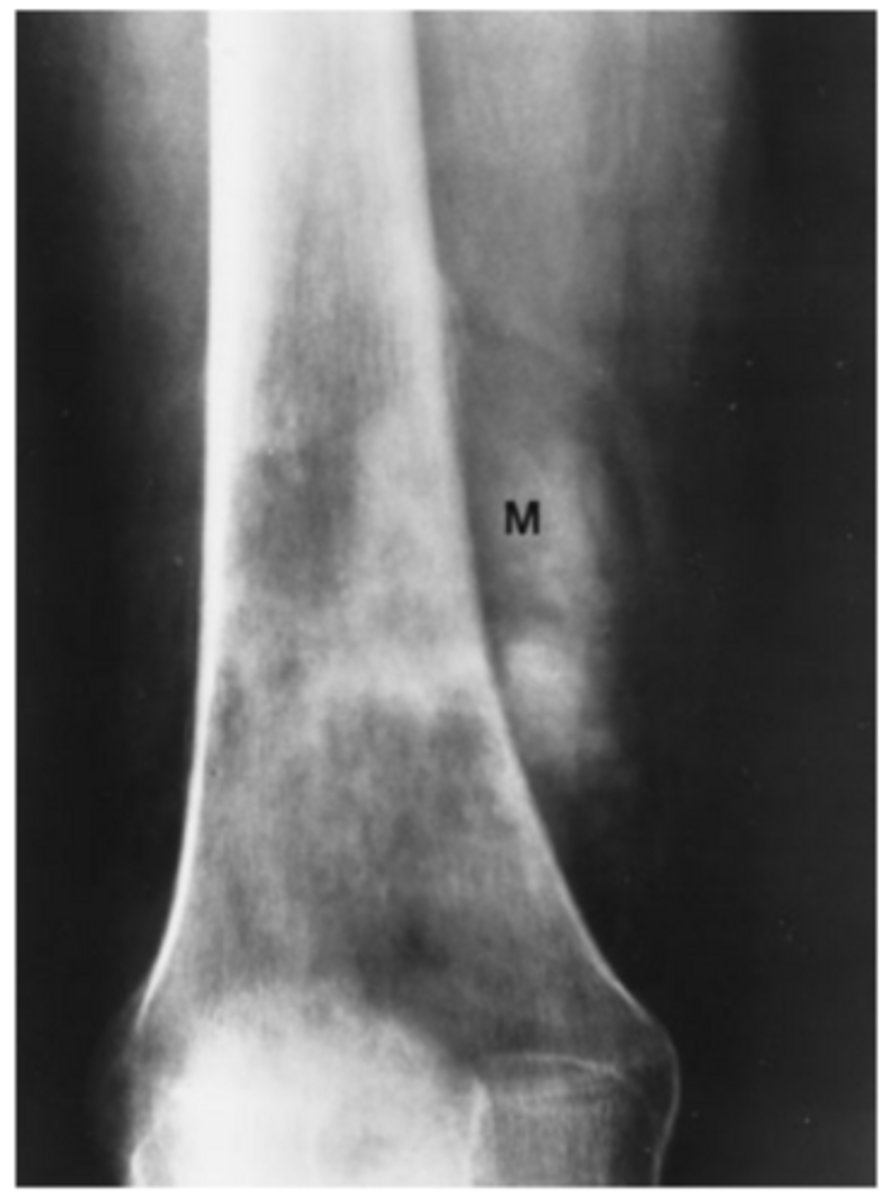

A 40-year-old man complains of knee pain and swelling of 3 weeks' duration. He has no other known disease. You order conventional radiographs of the knee.

For Case 6-11 (Figure 6-29), what is the next study

you should order?

A. Bone scan

B. MRI of the knee

C. Hand films

D. Chest radiograph

Answer

D.

A thin rim of calcium added to the bony contour of both sides of the right femoral metaphysis due to periosteal elevation. Similar findings are seen on the left femur and both tibiae

Periosteal elevation as seen in 6-11

Nonspecific finding that occurs with local disorders such as fracture, bone tumors, osteomyelitis, and bone infarction.

Hypertrophic osteoarthropathy

Characterized by chronic proliferative periostitis of long bones , clubing of fingers and synovitis, Its asso with Squamou cell carcnimoa and Adenocarcinoma of the lung.